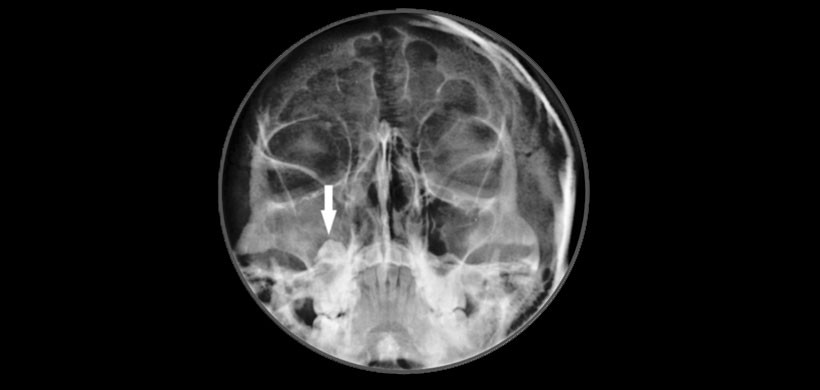

Se optó primero por realizarle una radiografía panorámica la cual muestra una radiolucides  que involucra el seno maxilar derecho junto con el tercer molar impactado (figura 1). Posteriormente se realizó una radiografía de senos paranasales para determinar que la piezas 18 este dentro del seno maxilar derecho (Figura 2) y finalmente se pudo comprobar mediante la tomografía computarizada y a su vez determinar el tamaño de la lesión así como las estructuras óseas y dentarias afectadas. (Figura 3)